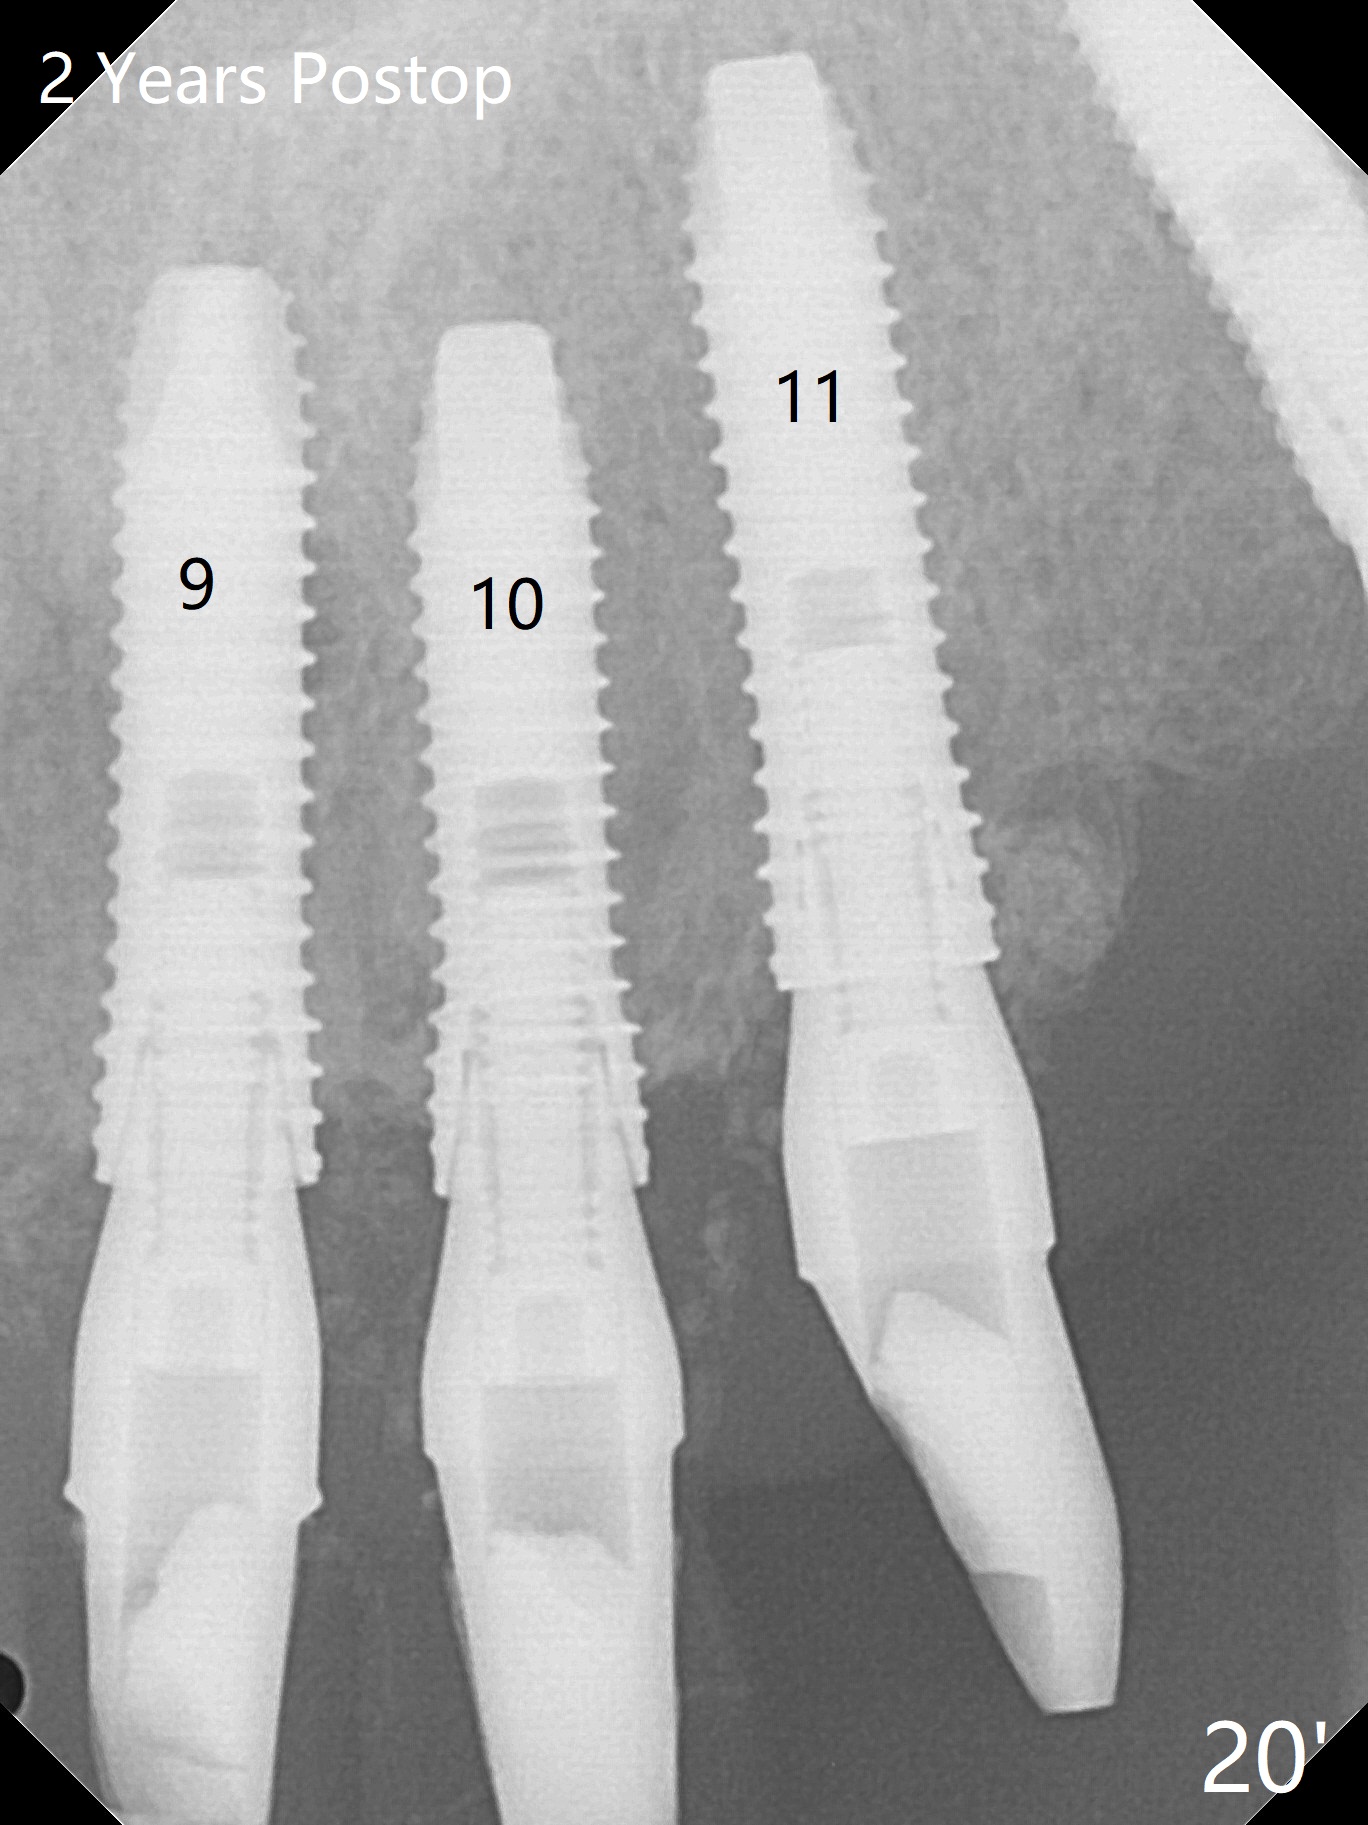

There is 1-2 thread exposure mesial and distal at #10 two years postop (Fig.20'), which may be related to the small fistula labially (Fig.20 >). It appears that the implant at #10 was placed too high (Fig.21) and labially (Fig.22). In fact the bridge fractures between #12 and 13 during pandemic.